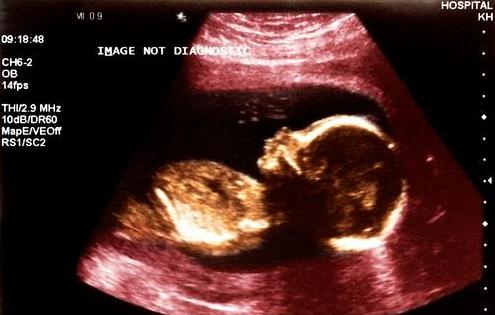

孕期应当做多少次B超检查?

虽然B超检查非常必要,但并不可以随意去做,一定要在医生指导下,在适当的时间接受适当的检查。从优生优育的角度来看,孕妇采用超声波检查的次数以2~3次为宜,不要超过3次。

一般情况下是20~24周做第一次排畸检查。怀孕早期。除了妇科的常规检查之外,应通过B超确定宫内的妊娠是否正常。例如宫腔内探查不到任何妊娠征象,而在子宫腔外探到异常的回声,结合其他的临床表现就可以诊断子宫外孕。所以一般提倡于怀孕早期通过做B超明确是否是宫内正常妊娠或双胎、葡萄胎等。

30~32周做进一步排畸,了解其发育情况并确定胎儿方位。怀孕中期。大约在闭经16周左右需要再做一次B超,以确定胎儿有无畸形和生长发育是否正常。因为如果这时发现胎儿不正常,在闭经20周以内中止妊娠,是比较适宜的。

最后一次建议在36~38周,分娩前确认下胎位、羊水以及胎盘等各种情况。怀孕晚期。即闭经36周以后,做B超可以明确羊水多少以及胎盘的功能。羊水过多或过少,以及胎盘钙化或功能不良,都不应再继续妊娠。必要时需进行剖腹产。